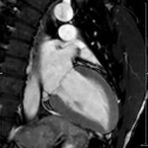

Herz/Thorax

Herz

Durchführung am Standort im Diakonissenkrankenhaus.

• kardiale Ischämiediagnostik mit medikamentöser Stress-MRT (Adenosin)

• Infarktnarbendarstellung/Vitalität

• Kardiomyopathien (z.B. Myokarditis, DCM, HCM/HOCM, Amyloidose, Sarkoidose)

• Klappenbeurteilung mit Phasenkontrastangiographie

• Tumoren Herz und Mediastinum

• Fehlbildungen

• MR-Angiographie zur Erfassung und Verlaufskontrolle von Aneurysmen der Aorta thorakalis und ihrer Gefäßabgänge